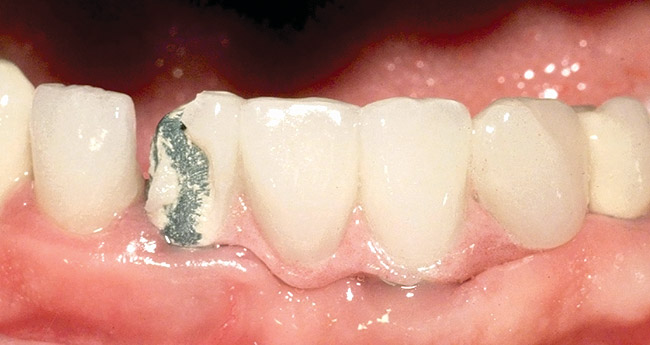

Figure 19  Labial view of an implant with a peri-implant soft-tissue depth of approximately 5 mm. This patient had lost the healing abutment and did not return for replacement before the definitive impression appointment. The implant restorative platform was not visualized, and the definitive implant-level impression could not be made as scheduled.

Figure 19